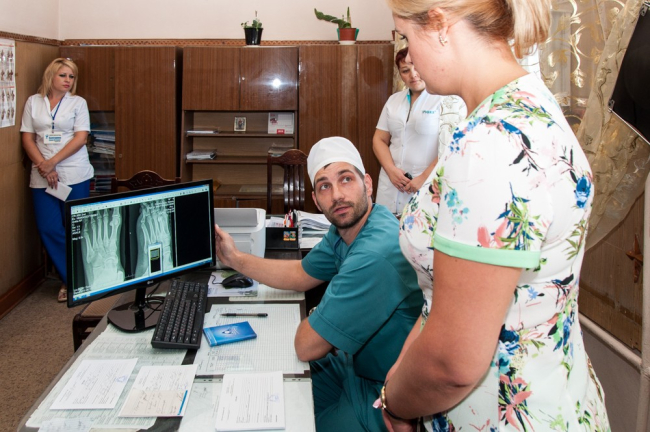

«Аппарат позволяет делать все виды рентгенологических исследований как в цифровом формате, так и в аналоговом, есть функция рентгеноскопии, которая позволяет прицелиться и найти труднодоступные места, чтобы их зафиксировать», – рассказал врач-рентгенолог приёмного отделения РКБ Олег Стамов.

При необходимости полученные снимки можно распечатать, но в большинстве случаев надобности в этом нет. Полученное изображение в течение считанных минут пересылается в электронном виде в травматологическое, хирургическое, реанимационное или онкологическое отделение прямо на компьютер лечащего врача. Потом его сохранят в базу данных – в личную папку пациента, чтобы легче было отслеживать историю его болезни.